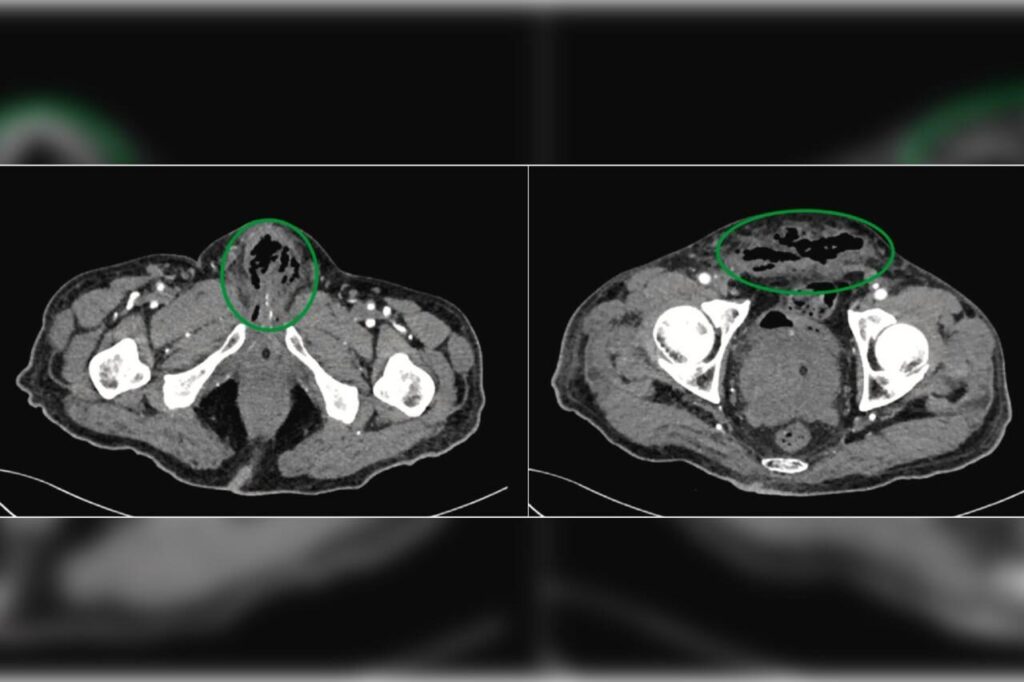

Um homem de 65 anos teve o pênis amputado após o órgão necrosar devido a uma infecção grave. O caso foi publicado no Urology Case Reports em 5 de agosto.